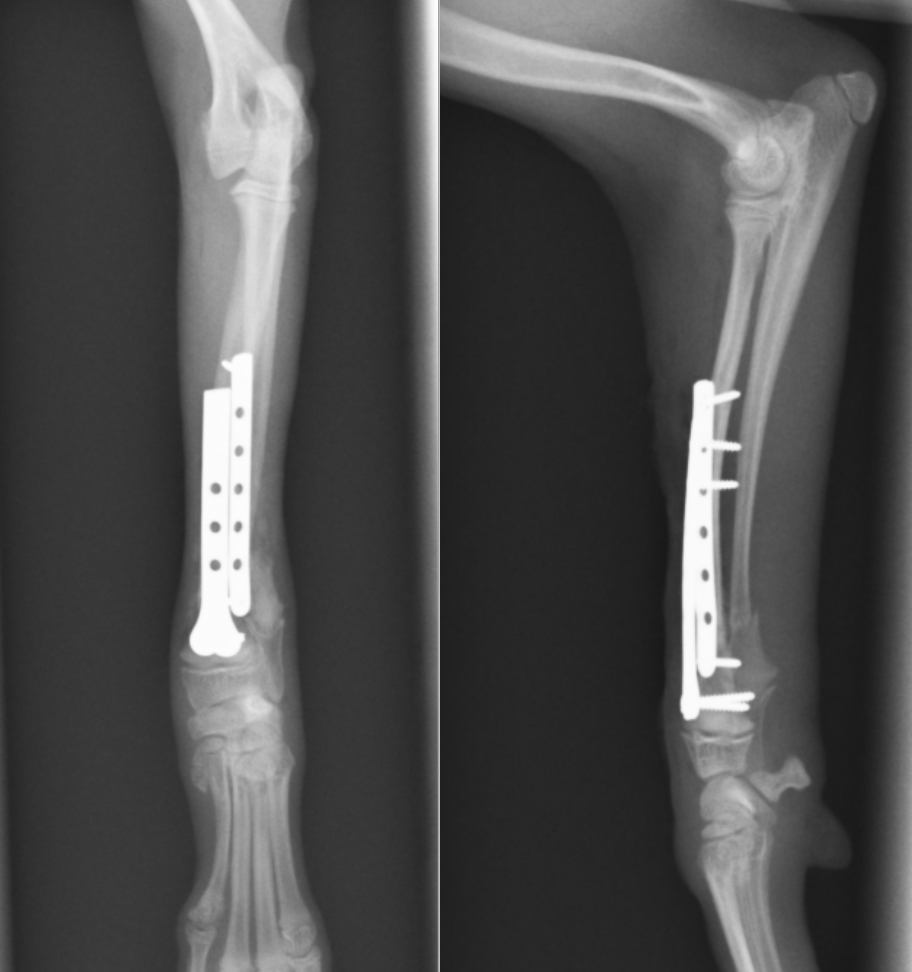

術後のレントゲン写真です。骨折部位はきちんと整復され、アライメント(骨の向き)も真っ直ぐになっています。

今回の子は体重1.7kgで骨も細かったため、1.3mmと1.1mmのプレート・スクリューを選択しました。このように、体重や骨の太さ、活動性に基づきプレートやスクリューを選択し、形に合わせてプレートを曲げたり、捻ったりして骨に合わせていきます。

2枚のプレートで固定しています。1つはLCPというプレートですが、スクリューは通常のスクリューを用いています。

術後のレントゲンです。足は真っ直ぐになり、骨折線もくっついているのが分かります。